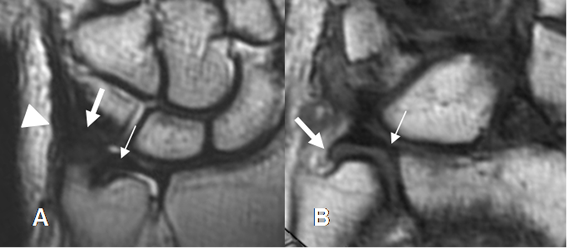

El FCT se identifica como una estructura bicóncava y en forma de corbatín, hipointensa en todas las secuencias. Se pueden ver sus inserciones en el radio y cúbito.

Sus componentes se identifican con la RM. El menisco, disco y ligamentos ulnopiramidal y ulnosemilunar se aprecian en vistas coronales. Los ligamentos radioulnar dorsal y volar se visualizan en el plano axial. (2). (Fig 22 y 23).

El menisco es una estructura hipointensa, con leve aumento normal de la señal sobre la inserción ulnar. (2).

Fig 22. Complejo del FCT normal.

A: RM coronal en T2. Cartílago (Flecha delgada), menisco homólogo (Flecha gruesa) y tendón del extensor ulnar del carpo. (Punta de flecha).

B: RM coronal en T2. Cartílago con su inserción radial (Flecha delgada) e inserción ulnar (Flecha gruesa).

Fig 23. Complejo del FCT.

A: RM axial en T1. Ligamentos radioulnar anterior (Flecha delgada) y radioulnar posterior (Flecha gruesa).

B: RM coronal en T2. Ligamentos ulnosemilunar (Flecha delgada) y ulnopiramidal (Flecha gruesa).